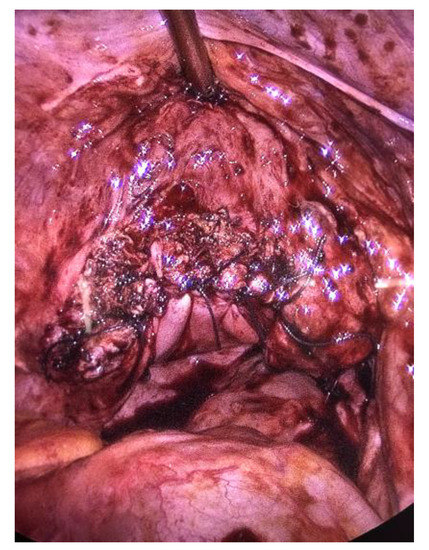

Objectives: The aim of this study is to demonstrate the efficacy of the modified technique of radical organ-preserving surgery of invasive cervical cancer (CC) in patients of reproductive age. Methods: This study included 118 patients of reproductive age (34.9 ± 4.8 [...] Read more.

Objectives: The aim of this study is to demonstrate the efficacy of the modified technique of radical organ-preserving surgery of invasive cervical cancer (CC) in patients of reproductive age. Methods: This study included 118 patients of reproductive age (34.9 ± 4.8 years) with a morphologically verified diagnosis of invasive CC (T1a-1bNxM0). All patients underwent organ-preserving surgery in the scope of radical trachelectomy. A shape memory mesh implant woven in the form of a stocking from superelastic nickelide titanium thread with subsequent fixation with separate sutures around the perimeter was used to form the uterine closure apparatus and to strengthen the utero-vaginal anastomosis. The mesh implant was made of superelastic thin nickelide titanium threads with a diameter of 60–40 microns on a metal knitting machine. All patients were prospectively followed up for a mean of 120 months. Results: No intraoperative or postoperative complications were revealed when using a shape memory implant made of titanium nickelide during radical trachelectomy to form a locking apparatus and strengthen the anastomosis zone. No cervical stenoses or mesh failures were noted in any case. The 5-year overall and recurrence-free survival rates were 100% and 98%, respectively. Two patients indicated recurrence; it occurred in 3 and 36 months. There were 42 spontaneous pregnancies, and 29 resulted in full-term delivery, whereas 2 and 11 ended in miscarriage and early abortion, respectively. Currently, 18 patients are at different stages of the use of assisted reproductive technologies. Conclusions: The shape memory implant made of titanium nickelide integrates well into the surrounding tissues and successfully imitates the effect of the cervix. The use of this sparing-surgery technique has shown reasonably good results in carrying the pregnancy to term and good reproductive outcomes. Full article

Show Figures

Figure 1